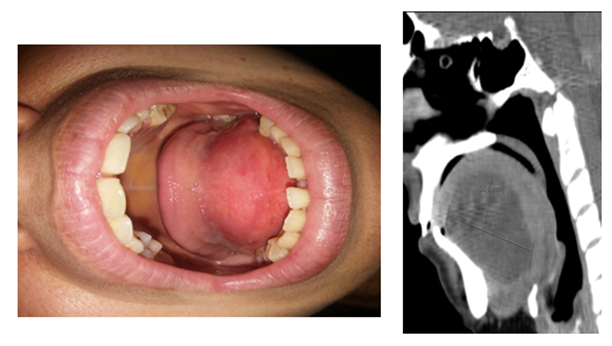

A female patient, 32 years old, non-smoker, went to the emergency department of our Otorhinolaryngology department with complaints of oral swelling, speech difficulties and progressive dysphagia for solids with about a month of evolution. No pain complaints, no dyspnea, no fever or similar episodes before. The patient also denied any surgical history or trauma to the oral cavity and any other relevant medical or personal history. On objective examination, a well-defined, symmetrical sublingual swelling was found, with no inflammatory signs, covered by normal-looking mucosa and about 3 cm in diameter (Image 1). Upon palpation, the lesion showed a soft consistency, with fluctuation and no associated pain. There were no signs of ulceration or other associated injuries. Due to the volume of the lesion, the tongue was displaced posteriorly. Upon cervical palpation, no adenopathies or other changes were identified. A CT scan was requested to better characterize the lesion in which a cystic mass about 6 cm in diameter could be seen, with homogeneous content located in the sublingual region, inferiorly limited by the mylohyoid muscle, with no relief after contrast (Image 2). No evidence of calculations or dilation of the submandibular duct, neither invasion of adjacent structures or adenopathies were found.